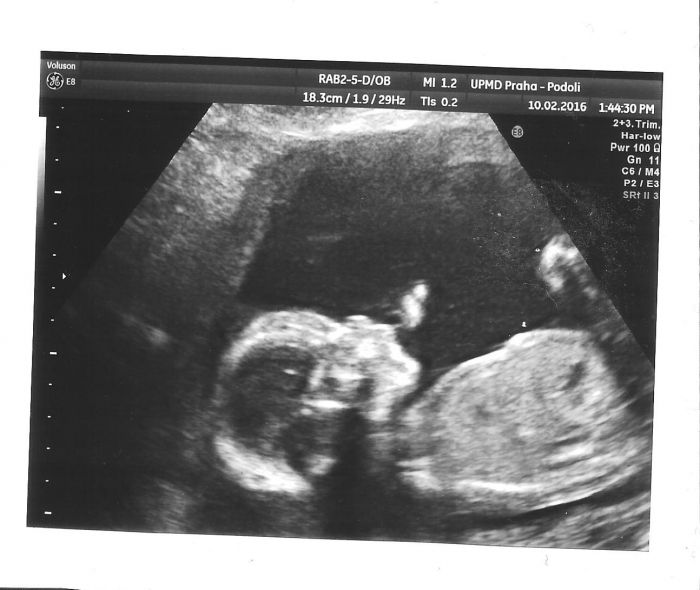

No a v 1 v Podolí na velkým ultrazvuku. Od gynekoložky jsem konečně dostala papír se všema výsledkama z 1. screeningu, tak večer budu študovat hodnoty, to já ráda :-) No a vzala jsem s sebou ten posudek z genetiky z minulého těhotenství, tam bylo doporučení pro ultrazvukáře co pořádně prohlédnout, aby se vyloučily ty poruchy, co maj naši. Takže z máminý strany jde hlavně o dlouhé kosti v končetinách a z tátový strany o páteř, srdce a ledviny. Tak si to pročetli a prohlídli mi miminko opravdu pořádně a všechno je tak jak má být, nic není v nepořádku, mimi je o něco větší, ještě budu muset prozkoumat všechny ty míry, protože jedna je až úplně za hranicí mimo stupnici, jestli to je obvod hlavy? No ještě kdyžtak napíšu. Řekla jsem, že nechceme aby nám říkal pohlaví, že bychom rádi, aby to byl chlapeček, ale že se radši necháme překvapit až na sál. Že se jen budu koukat a buď si tam něco vykoukám mezi nožičkama nebo ne. No a tak jsem koukala, projížděl sondou od bříška přes rozkrok až na zadeček, a zdálo se mému totálně amatérskému a nezkušenému zraku, že tam v tom rozkroku bylo nějak moc plno. Že tam toho bylo nějak jako moc hmoty. Na konci se doktor ještě ptal 2x, jestli teda fakt nechci pohlaví vědět a byla jsem tvrdá a řekla jsem, že ne. Placentu mám na zadní stěně a zasahuje do branky. No hlavně že není vepředu, to by mě nemohli říznout. Takhle to je dobrý a půjde to i dobře vyndat tu placentu :-) No a jizva je prej naprosto v pořádku, žádný ztenčení tam není, je zcela zhojená a v pořádku. Takže samé dobré zprávy! :-) Byla se mnou velká dcera a moc se jí to líbilo a všichni byli slušní a milí a příjemní.